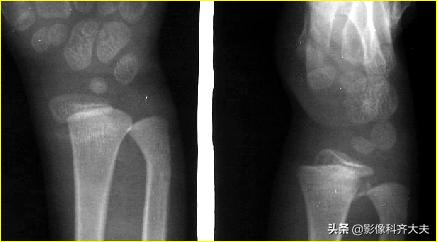

Colles骨折:伸展型桡骨远端骨折,在桡骨远端2-3cm以内的横行或粉碎骨折,远侧向桡或背侧移位,常合并尺骨茎突骨折。